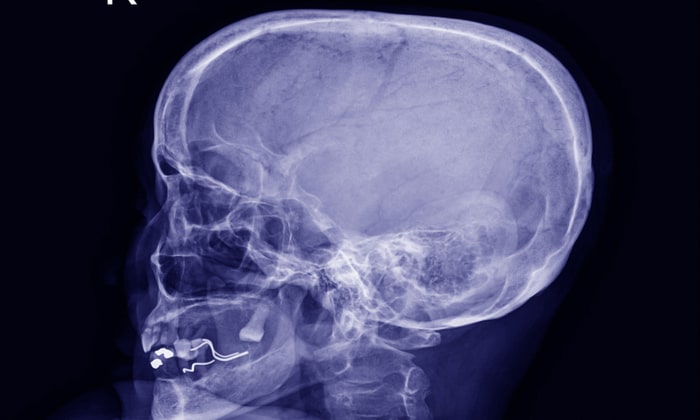

โรคลมเข้าสมอง (Pneumocephalus) คืออะไร

โรคลมเข้าสมอง (Pneumocephalus) เกิดขึ้นจากการที่มีอากาศเข้าไปภายในสมองแล้วค้างอยู่ภายในสมอง โดยมีสาเหตุเกิดจากปัจจัยหลาย ๆ อย่าง เช่น หลังจากการผ่าตัดกะโหลกศีรษะ อุบัติเหตุที่ศีรษะหรือที่เกี่ยวข้องกับฐานกะโหลกศีรษะ เนื้องอกฐานกะโหลกศีรษะ เป็นต้น

การทำซีที สแกน (Computerized Tomography Scan) จะช่วยให้เราสามารถตรวจหาอากาศที่ถูกเก็บไว้ในสมอง จะเห็นถึงอากาศที่ถูกอัดอยู่ในสมองส่วนหน้า เป็นสัญลักษณ์ของภูเขาไฟฟูจิ โดยชื่อนี้ได้มาจากความคล้ายคลึงของสมองที่เหมือนกับภูเขาไฟฟูจิ ในประเทศญี่ปุ่น